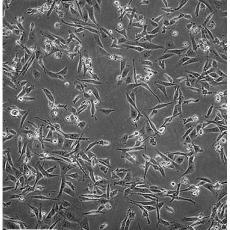

中文名稱 人乳腺癌細胞

組織來源 乳腺腺癌;胸腔積液轉移;女性

形態(tài)特征 epithelial

細胞描述 MDA-MB-231來自患有轉移乳腺腺癌的51歲女病人的胸水。在裸鼠和ALS處理的BALB/c小鼠中,它能形成低分化腺癌(III級)。